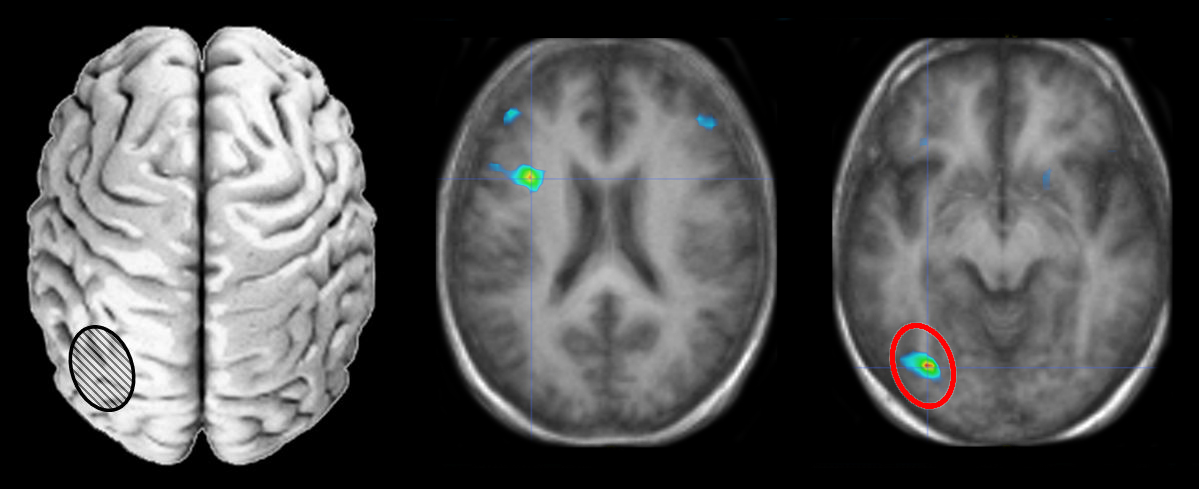

Neurosciences

Images et documents en rapport avec les articles

scenar6

Ancien logiciel : EduAnatomist et Neuropeda

Informations sur les images AnaPeda